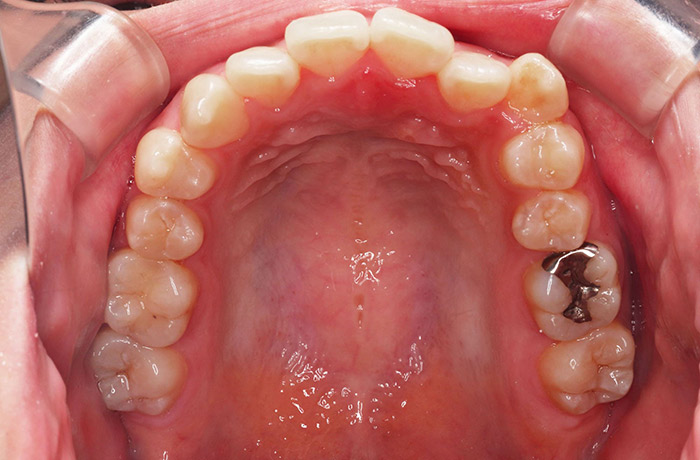

M様

治療前

before

年齢 21歳

性別 男性

治療名称 マウスピース型カスタムメイド矯正歯科装置(インビザライン)・コンプリヘンシブパッケージ(フルパッケージ)

総額治療費用 770,000円(税込10%) 金額備考 精密検査料・診断料 33,000円(税込10%)

治療期間 1年 通院頻度など 1か月ごと

患者の症状 上顎前突、前歯離開

治療方法 マウスピース型カスタムメイド矯正歯科装置(インビザライン)による矯正

治療結果 歯列改善、咬合状態が良くなりました。

※治療結果は患者様によって個人差があります。

リスク/副作用 20時間以上、装置の装着時間が必要です。